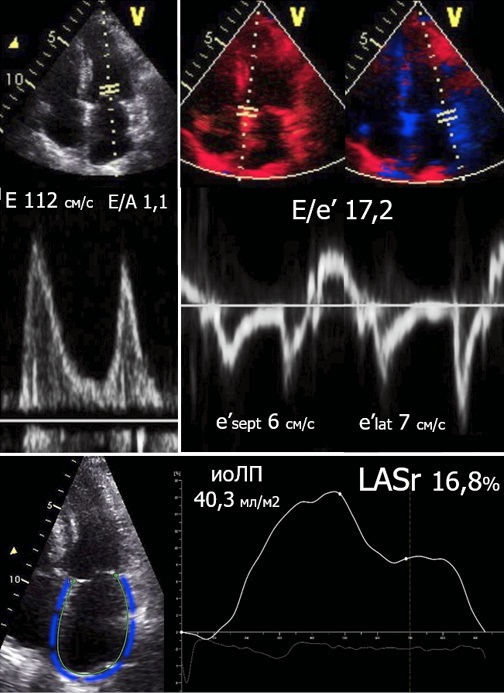

ДСТ позволяет выявить больных СНсФВ с незначительным ремоделированием сердца (ранняя/своевременная диагностика). По нашим данным, такие пациенты менее чем в 50% случаев имеют дилатацию полости ЛП, у них отсутствуют признаки ЛГ в покое. При этом умеренное угнетение резервуарной функции ЛП (LASr <24% [12]) выявлено у 70% пациентов. Напротив, больные СНсФВ с более значимой ДД, выявленной без проведения стресс-теста, в большинстве имеют расширение ЛП и выраженное снижение LASr <18% [12], сочетающиеся с увеличением массы миокарда ЛЖ (рис. 4). В этом контексте важно указать на NT-proBNP, уровень которого значимо растет при продолжающемся структурно-функциональном ремоделировании сердца [2].

Рис. 4. Анализ диастолической функции ЛЖ с определением выраженного увеличения среднего давления полости ЛП в состоянии покоя: E/e′ >14, LASr <18%, иоЛП >34,0 мл/м².

Примечание: цветное изображение доступно в электронной версии журнала.

Сокращения: иоЛП — объем левого предсердия, индексированный по площади поверхности тела, LASr — Left Atrial reservoir Strain (деформация резервуарной фазы левого предсердия).